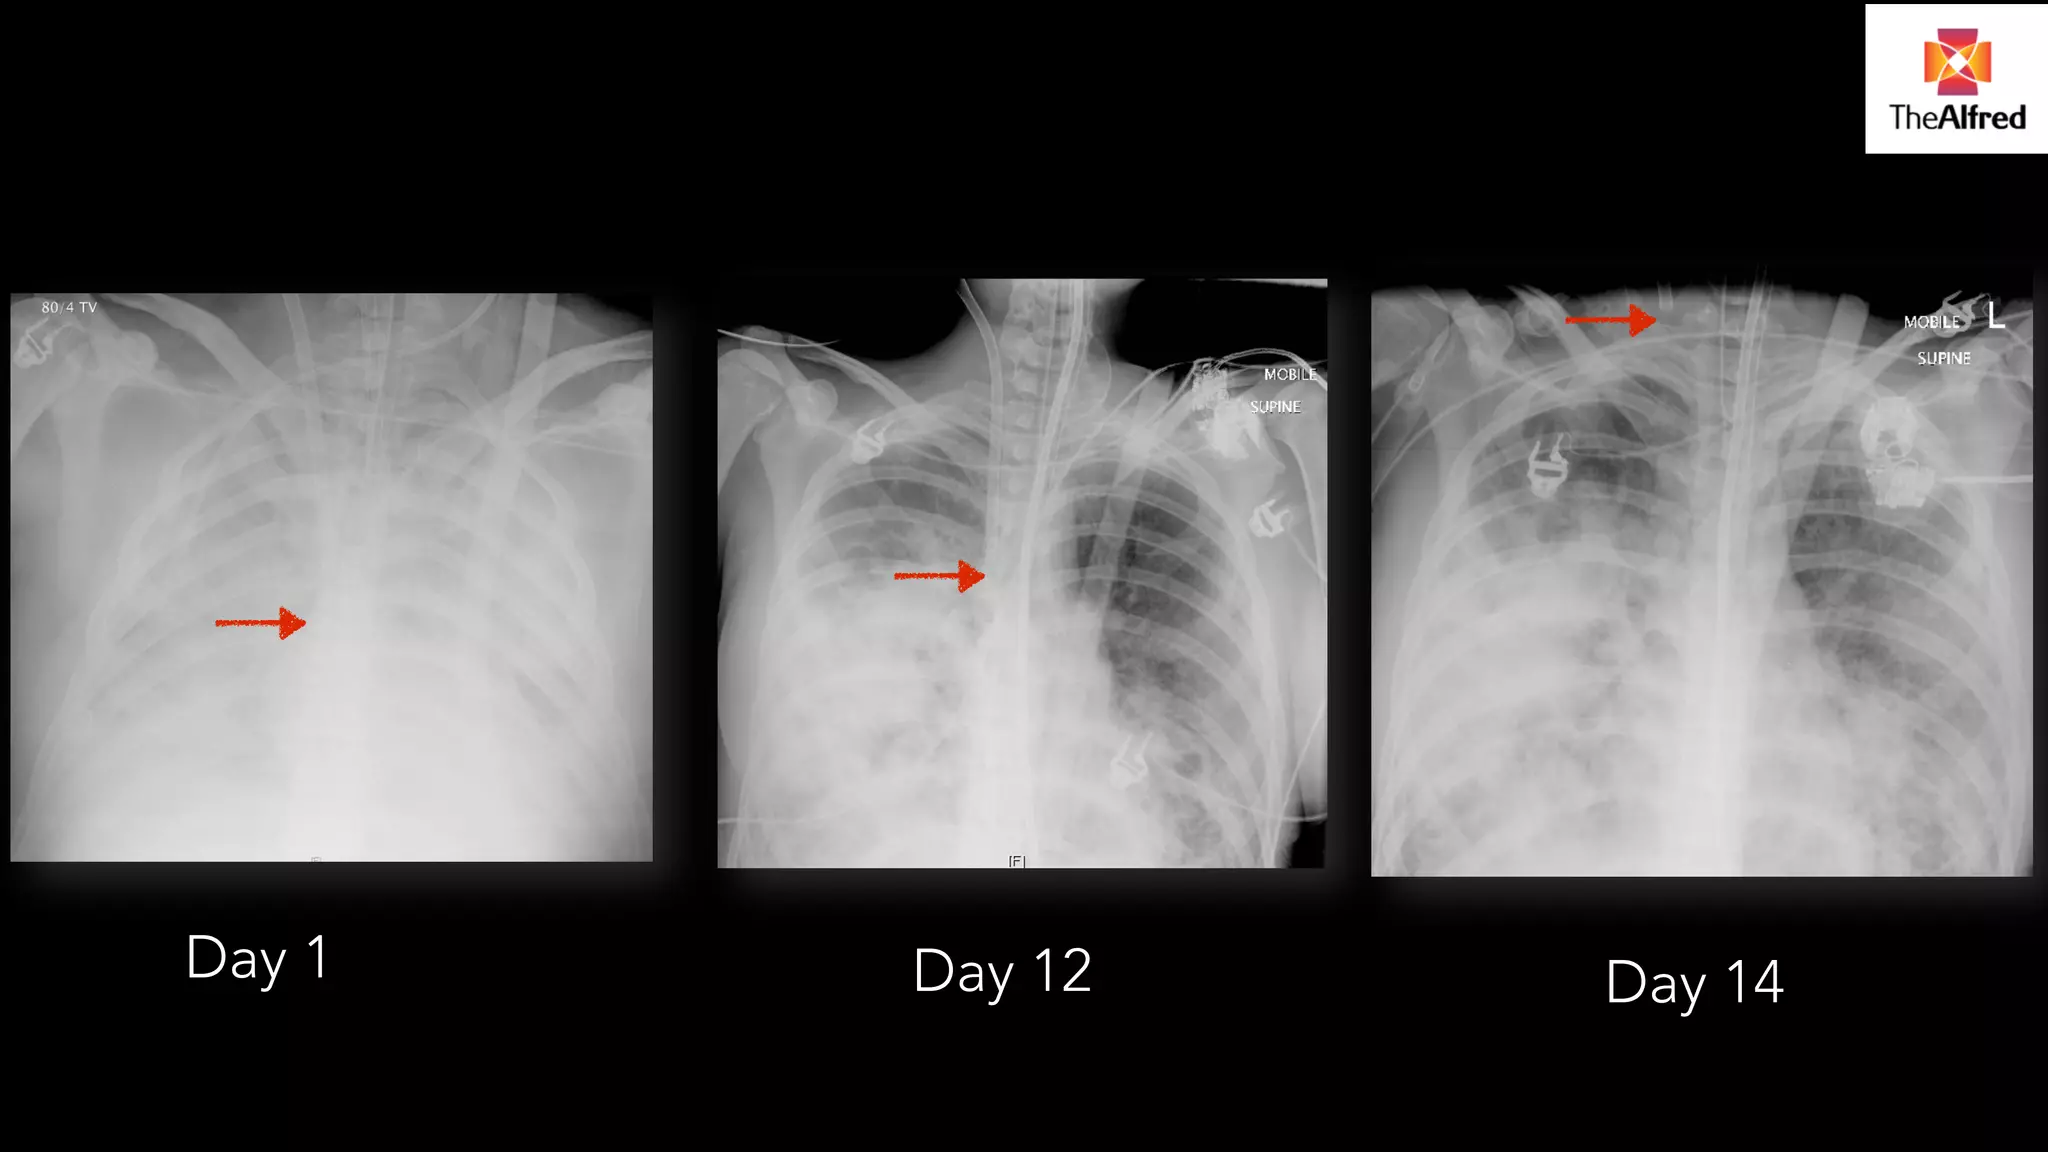

Day 1 Day 12 Day 14

MAINTENANCE PHASE..AT THEWORST POSSIBLE MOMENT. . Circuit complications disruption of circuit venous (pre-pump) arterial (Post pump) All life threatening emergencies

Day 1 Day12 Day 14